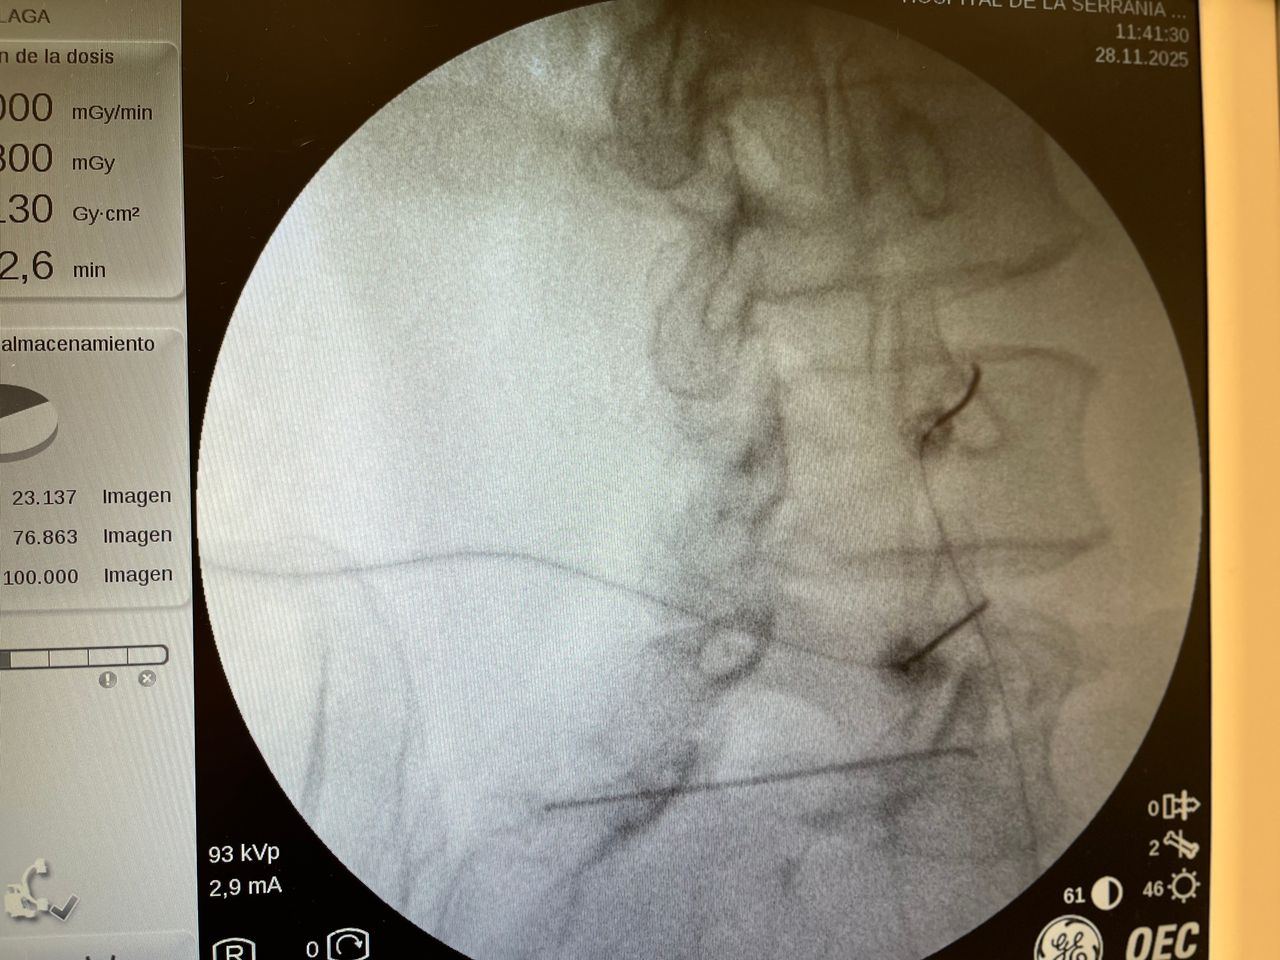

Galería